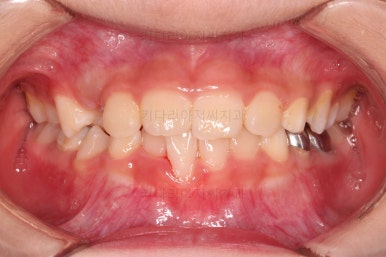

Case 1. 전/후

CASE 1.

나이 : 9세

총 치료기간 : 3개월

초진 시 얼굴사진인데요.

이번 환자분은 다행히 뼈의 문제는 없는 것으로 판단이 되었는데요.

그래서 이번 환자분도 뼈의 문제는 없지만 앞니가 거꾸로 물리는 건 개선해주자고 했죠.

바로 전후 비교사진 올립니다.

골격의 문제가 없었고 골격에 대한 치료가 아니었지만 얼굴 모습도 약간의변화가 있죠?

함몰감이 약간 있던 윗입술 부분이 볼륨감이 생기면서 자연스러운 아이얼굴 비율이 되었어요.

치열도 자연스럽게 예뻐졌네요.

3개월만에요😄